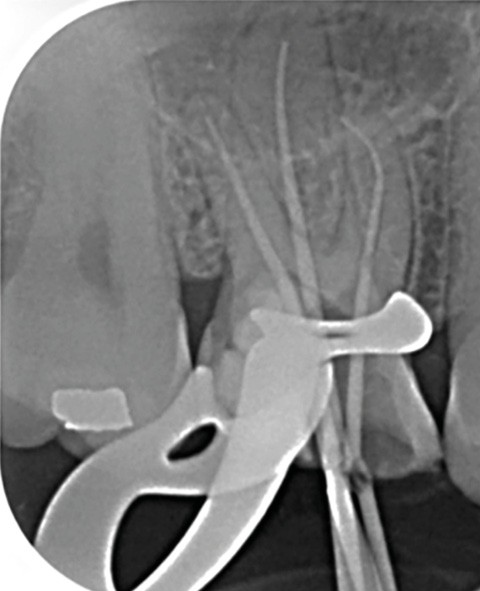

13. si possible, mise en place d’un champ opératoire sur la dent concernée, de sorte à isoler la zone de perforation de toute humidité (fig. 2) ;